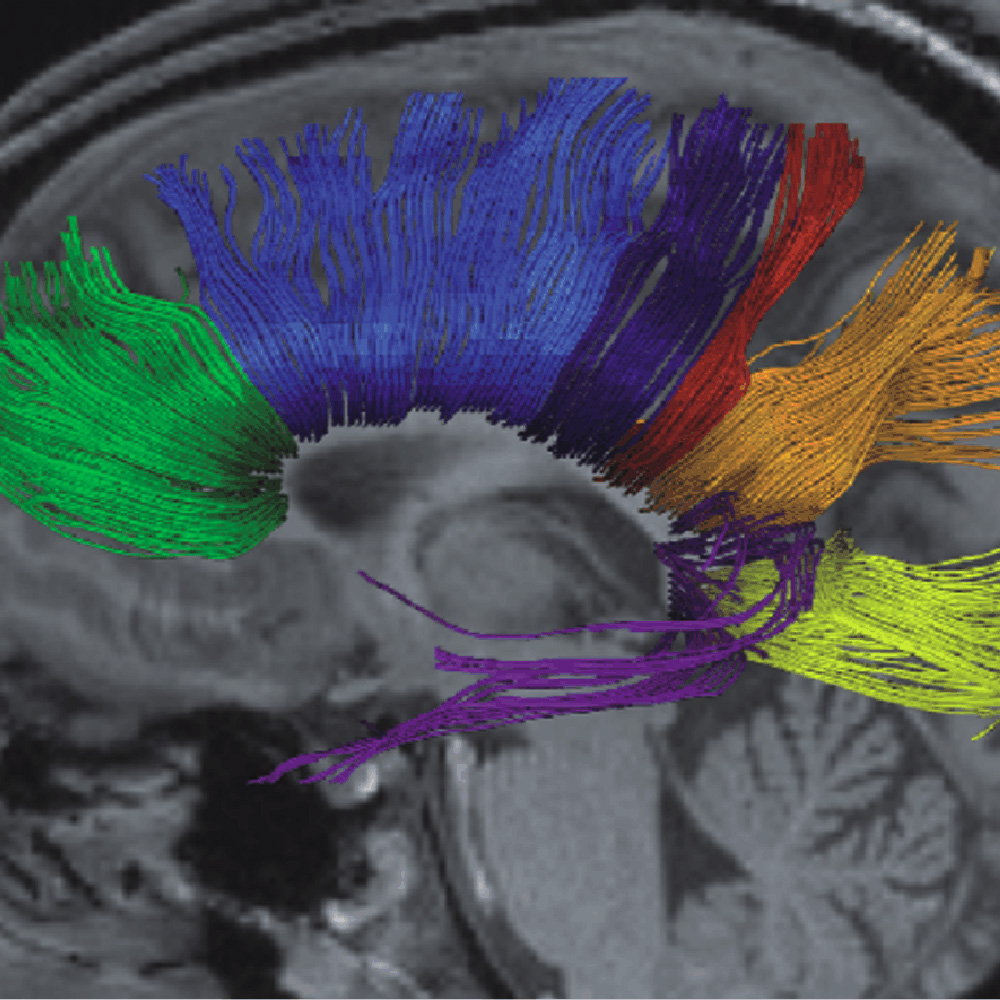

Fiber tracks in the human brain (© MPI for Biophysical Chemistry)